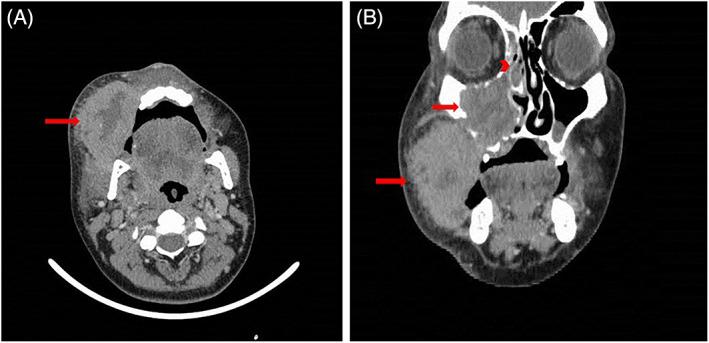

Peripheral T-Cell Lymphoma Not Otherwise Specified (PTCL-NOS) is a rare type of non-Hodgkin T-cell lymphoma which frequently seen in immunocompromised individuals. It is estimated that only 2% of lymphomas are located on the buccal mucosa. In this case report, we present a 34-year-old male with a PTCL diagnosis.

A 34-year-old immune-competent male presented with a buccal progressive ulcerated lesion. Histopathologic and immunohistochemical findings were compatible with PTCL-NOS and classified as stage IIEA according to the Ann Arbor staging. The patient underwent chemotherapy followed by radiotherapy. He remained disease-free after 12 months of follow-up.

一位 34 岁免疫功能正常的男性出现颊部进行性溃疡性病变。组织病理学和免疫组织化学检查结果与 PTCL-NOS 相符,并根据安阿伯分期系统分类为 IIEA 期。患者接受了化疗,随后进行了放疗。在 12 个月的随访中,他无疾病复发。